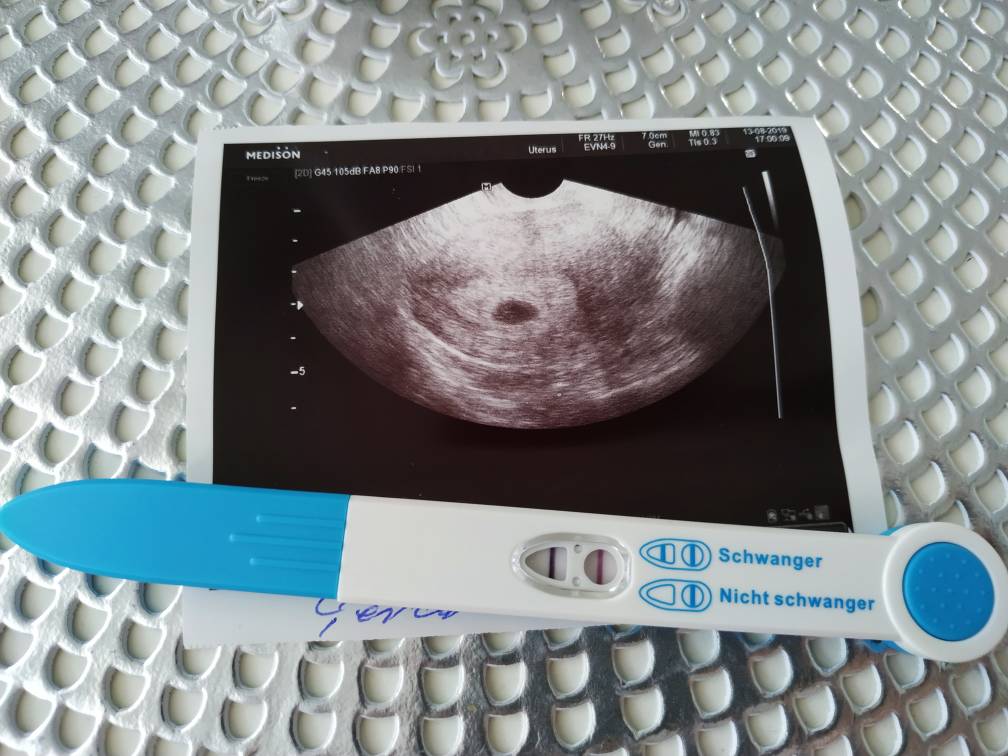

Chodzisz do lekarza u siebie w mieście?@Karolina2102 takie COSIK miałam na 1 wizycie, napewno już podrosło. Następna wizyta 3go września już na mierzenie zarodka [emoji846]Zobacz załącznik 1012937